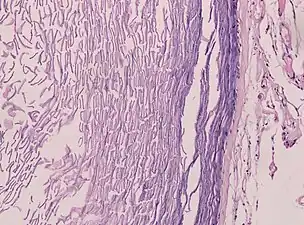

Histopathology, showing a keratinizing stratified squamous epithelium, and a lumen containing keratin flakes

Histopathology showing epithelium and lamellated keratin (left)